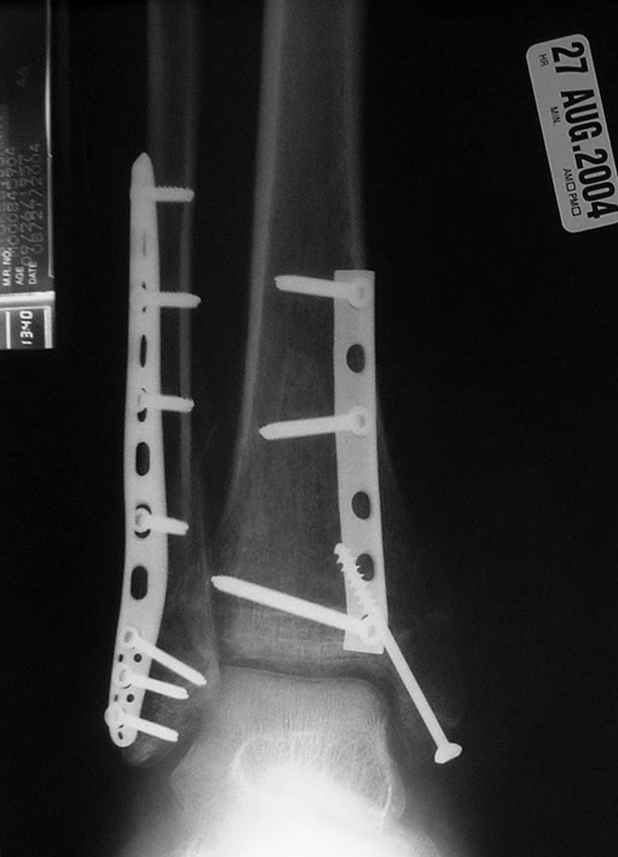

Отправитель: Djoldas Kuldjanov, M.D. 16 Сентябрь 2004, 22:00

Второй случай сделан из одного разреза

Дж

ЕЧ LISS plate, mininvasive approach - luxurous !

На прямой проекции послеоперационного Рг макроскопически все выглядит очень анатомично, при микроскопическом ( :-)) ) рассмотрении можно все-таки заметить вальгизацию тарана, суставная щель в латеральном отделе сустава несколько уже , чем в медиальном при отсутствии латерального смещения тарана. У меня был аналогичный случай (без LISS , без мини доступа) с вальгусным наклоном тарана при восстановленном ankle mortise при последовательном наблюдении с интервалами в 6-8 недель в послеоперационном периоде отмечалось прогрессирующее сужение суставной щели в латеральном отделе сустава, закончившееся посттравматическим ОА, к счастью боли умеренные, купируемые аналгетиками или своими эндорфинами:-))(активная пациентка, у которой нет времени на болезни....) Какова жизненная ситуация в приведенном вами случае? И последнее, что я хотел бы прояснить для себя - фиксация внутренней лодыжки: я обычно комбинирую фиксацию компрессирующим винтом со спицей - по идее ротационная стабильность должна быть лучше, чем один винт, каковы ваши наблюдения в этом плане?